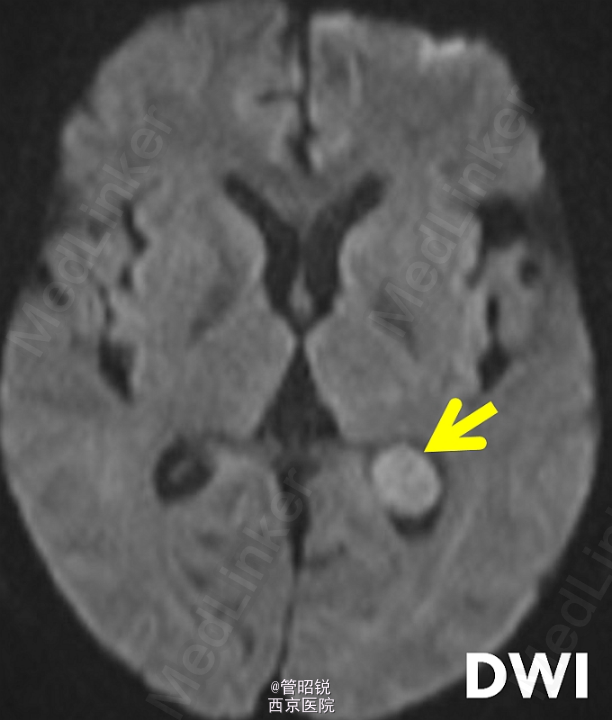

脑室内脑膜瘤占脑膜瘤的0.5%-3%,主要分布在三角区。常发生于中老年女性。原始瘤细胞被认为起源于蛛网膜帽细胞,常常表现为交感神经异常的相关症状,或者症状多变。经典的影像学结果包括CT高密度团块、T2孤立的低信号影、T1WI强化后显示均匀增强。需同转移瘤、淋巴瘤和囊虫病相鉴别。来源于AJNR